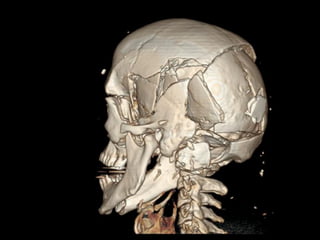

■ CRANE ET FACE

Os de la face et du crane

Le squelette de l’extrémité céphalique

est constitué de 3 éléments :

(vue latérale droite)